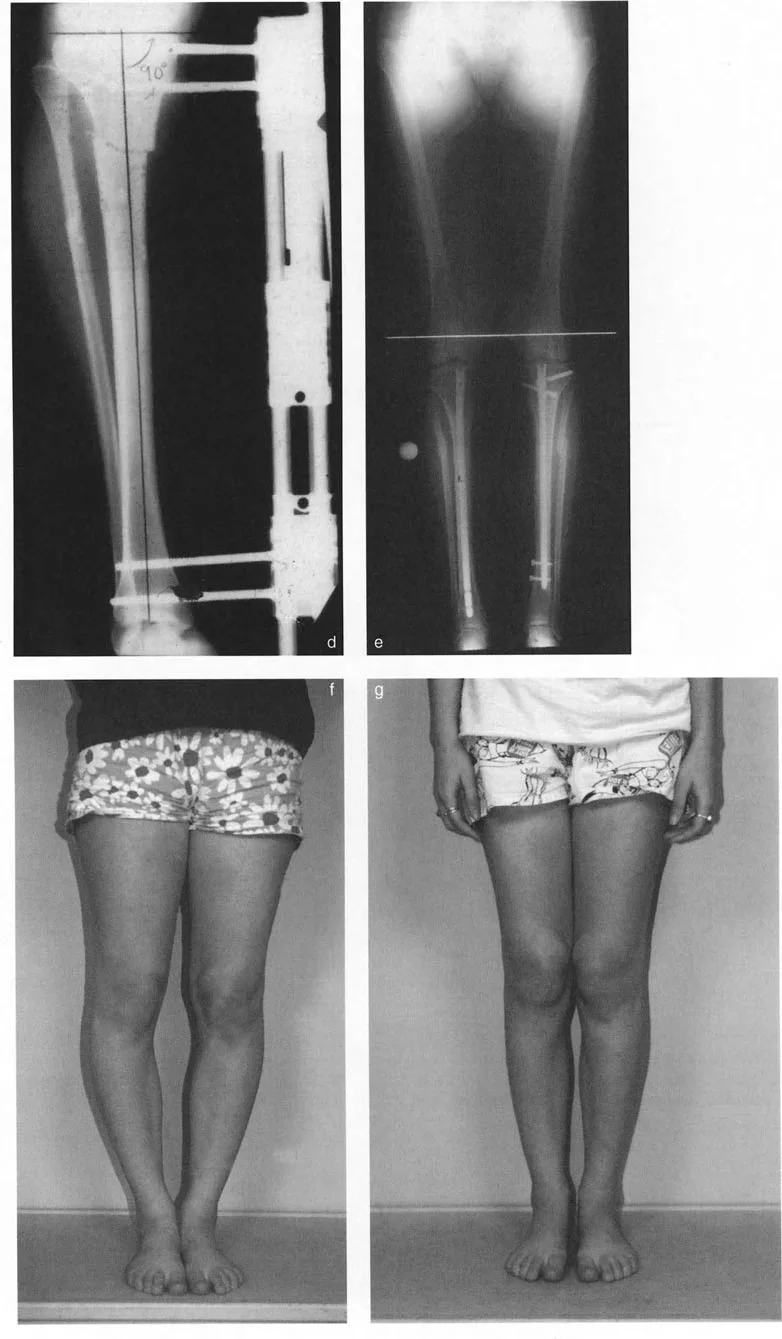

توضح التسلسلات السريرية أعلاه ببراعة القوة العميقة لقطع العظم القُببي البؤري جنبًا إلى جنب مع تطبيق الأجهزة الاستراتيجية.

* الحالة قبل الجراحة (f): تُظهر الصور السريرية تشوهات شديدة في تقوس الساقين الثنائي (genu varum)، مما أدى إلى انحراف هائل في المحور الميكانيكي الإنسي.

* التنفيذ أثناء الجراحة (d): باستخدام مثبت أحادي الجانب إنسي، يتم تصحيح تشوه الساق بدقة بعد قطع العظم القُببي البؤري الغالق. لاحظ التوضع العظمي المثالي في موقع قطع العظم.

* النتيجة بعد الجراحة (e & g): تُظهر الصور السريرية الناتجة بعد الجراحة (g) والأشعة السينية الطويلة الواقفة (e) محاذاة ثنائية خالية من العيوب. لقد تم استعادة المحور الميكانيكي بشكل مثالي إلى مركز مفاصل الركبة، مما أدى إلى تحييد القوى المشوهة على الأجزاء الإنسية.